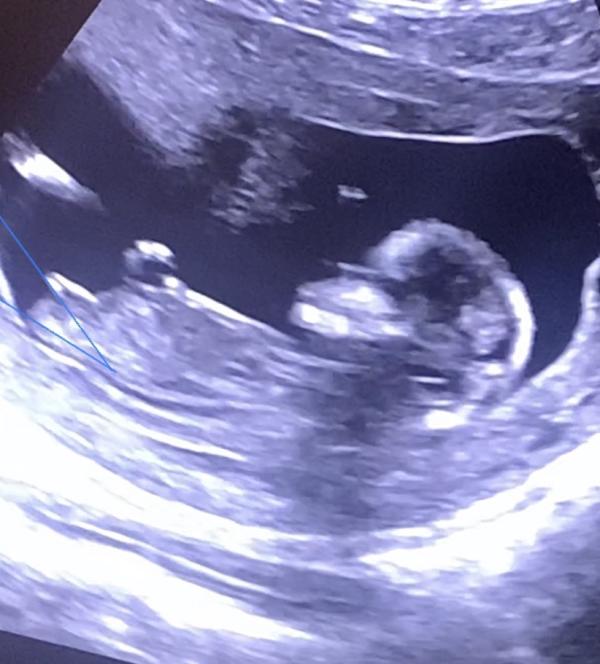

Девочки 😅давайте погадаем 😂🤣как думаете мальчик или девочка ?🤣пол незнаю 🤪ещё неделя и пойду на узи 😅но уже не терпится 🤣👌🏻🤪😁фотку успела сфоткать из клипа , который дали снять 🤣

Запись на память❤️

Нам почти 29 недель, что имеем: